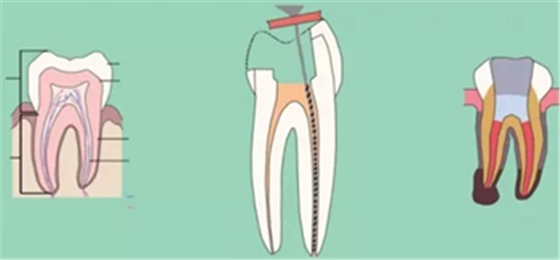

二、根管預(yù)備后形態(tài)

牙體缺損的修復(fù)需要將剩余牙體組織制備成一定形態(tài),以利修復(fù)體的良好固位。根管充填為了致密封閉根管系統(tǒng)也需要良好的根管預(yù)備后形態(tài)。

常規(guī)概念的根管預(yù)備后形態(tài)有:

( 1 )便宜形態(tài)( convenience form )

( 2 )保持形態(tài)( retention form )

( 3 )抵抗形態(tài)( resistance form )

1. 便宜形態(tài)

便宜形態(tài)是自切端或咬頜面朝向根尖的直線開擴(kuò)尖錐形態(tài),減少污染物推出根尖孔,方便沖洗、根管充填和側(cè)壁施壓。

2. 保持形態(tài)

保持形態(tài)是根尖狹窄部內(nèi) 1 — 2mm 的一段距離,由擴(kuò)大器回轉(zhuǎn)切割而不貼根管壁提拉切割制成,是擴(kuò)大器的原始形態(tài)(近似平行)。在測試主牙膠尖時給測試者有一個牽引抵抗 (tugback) 的感覺。

3. 抵抗形態(tài)

抵抗形態(tài)是根管預(yù)備的根尖形態(tài),它是由擴(kuò)大器或根管銼尖端 75 度角自然切割而成。其目的是防止根管充填材超出根尖孔,并且使根尖封閉更加嚴(yán)密。

三、開髓孔

1. 正常開髓孔的位置和大小

左圖為正常開髓孔的大小和位置。左邊圖為下顎,右邊圖為上顎。